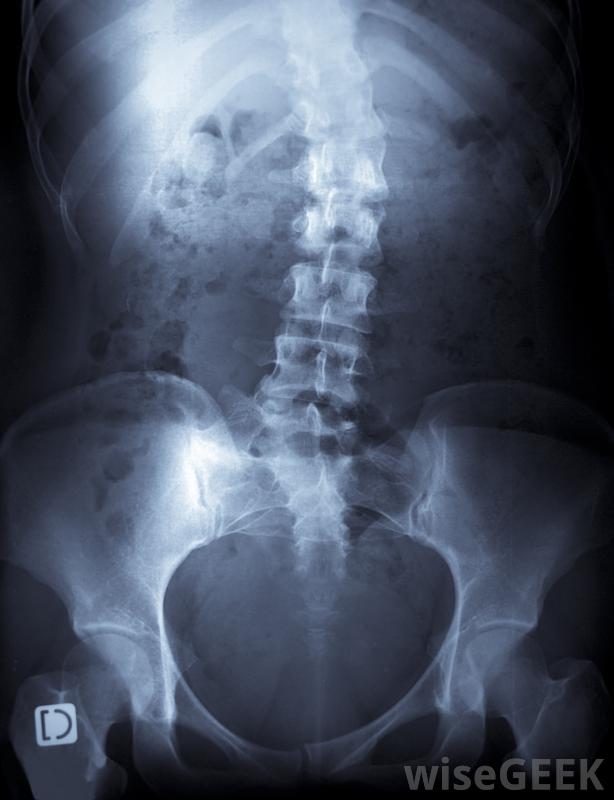

脊柱側凸物理療法是一種保守的治療脊柱側凸的方法,脊柱側凸是一種以脊柱彎曲為特征的骨骼疾病,物理療法可以與其他治療方法相結合,也可以單獨使用,根據患者的情況和推薦的治療方法,醫學界對脊柱側凸的治療效果存在一些爭論。一些研究表明,物理療法對某些類型的病例有幫助,應該被認為是一種可行的治療選擇脊柱側凸的物理治療可采用推拿和手法操作特發性脊柱側凸,也就是說沒有已知的彎曲原因。脊柱在童年或青春期早期開始向一側或另一側彎曲,脊柱側彎會變得非常嚴重。脊柱側凸的治療通常集中在阻止曲度的發展上。治療方案的使用取決于具體病例的具體情況。一般來說,干預越快,患者可能的結局越好,這也是為什么建議對幼兒進行脊柱側凸檢查的原因之一,以便盡早發現脊柱彎曲。脊柱側凸會導致脊柱彎曲在脊柱側彎理療的情況下,患者定期與理療師合作,并在家中進行鍛煉,有時在家人的協助下進行。重要的是要看有脊柱側凸理療經驗的理療師,人們通常會與臨床醫生和物理治療師同時工作,以確保治療過程保持適當和有效。如果正確、小心地進行,瑜伽有助于保持脊椎的柔韌和強壯。在物理療法中,患者需要通過伸展和彎曲來提高柔韌性、力量和音調,為了減少炎癥。患者可以被鼓勵做瑜珈和類似的運動,理療師可以在脊柱側凸理療課程中提供按摩和手動操作。家庭鍛煉旨在幫助身體保留物理治療的益處許多物理治療練習旨在減少炎癥和提高靈活性。對于輕度脊柱側凸,物理治療可以幫助阻止脊柱彎曲在其他情況下,脊柱側凸的物理治療可能需要配合支撐和更具攻擊性的治療,如手術。醫生可以評估患者,以確定哪種治療方案最有幫助,在制定治療計劃的同時,還可以對護理人員提出建議,以供參考。人們應該小心,確保對他們進行了脊柱側凸潛在原因的評估,由于某些原因會使治療復雜化。在輕度脊柱側凸的情況下,物理療法可以幫助阻止脊柱彎曲物理療法可能有助于減輕脊柱側凸的疼痛。